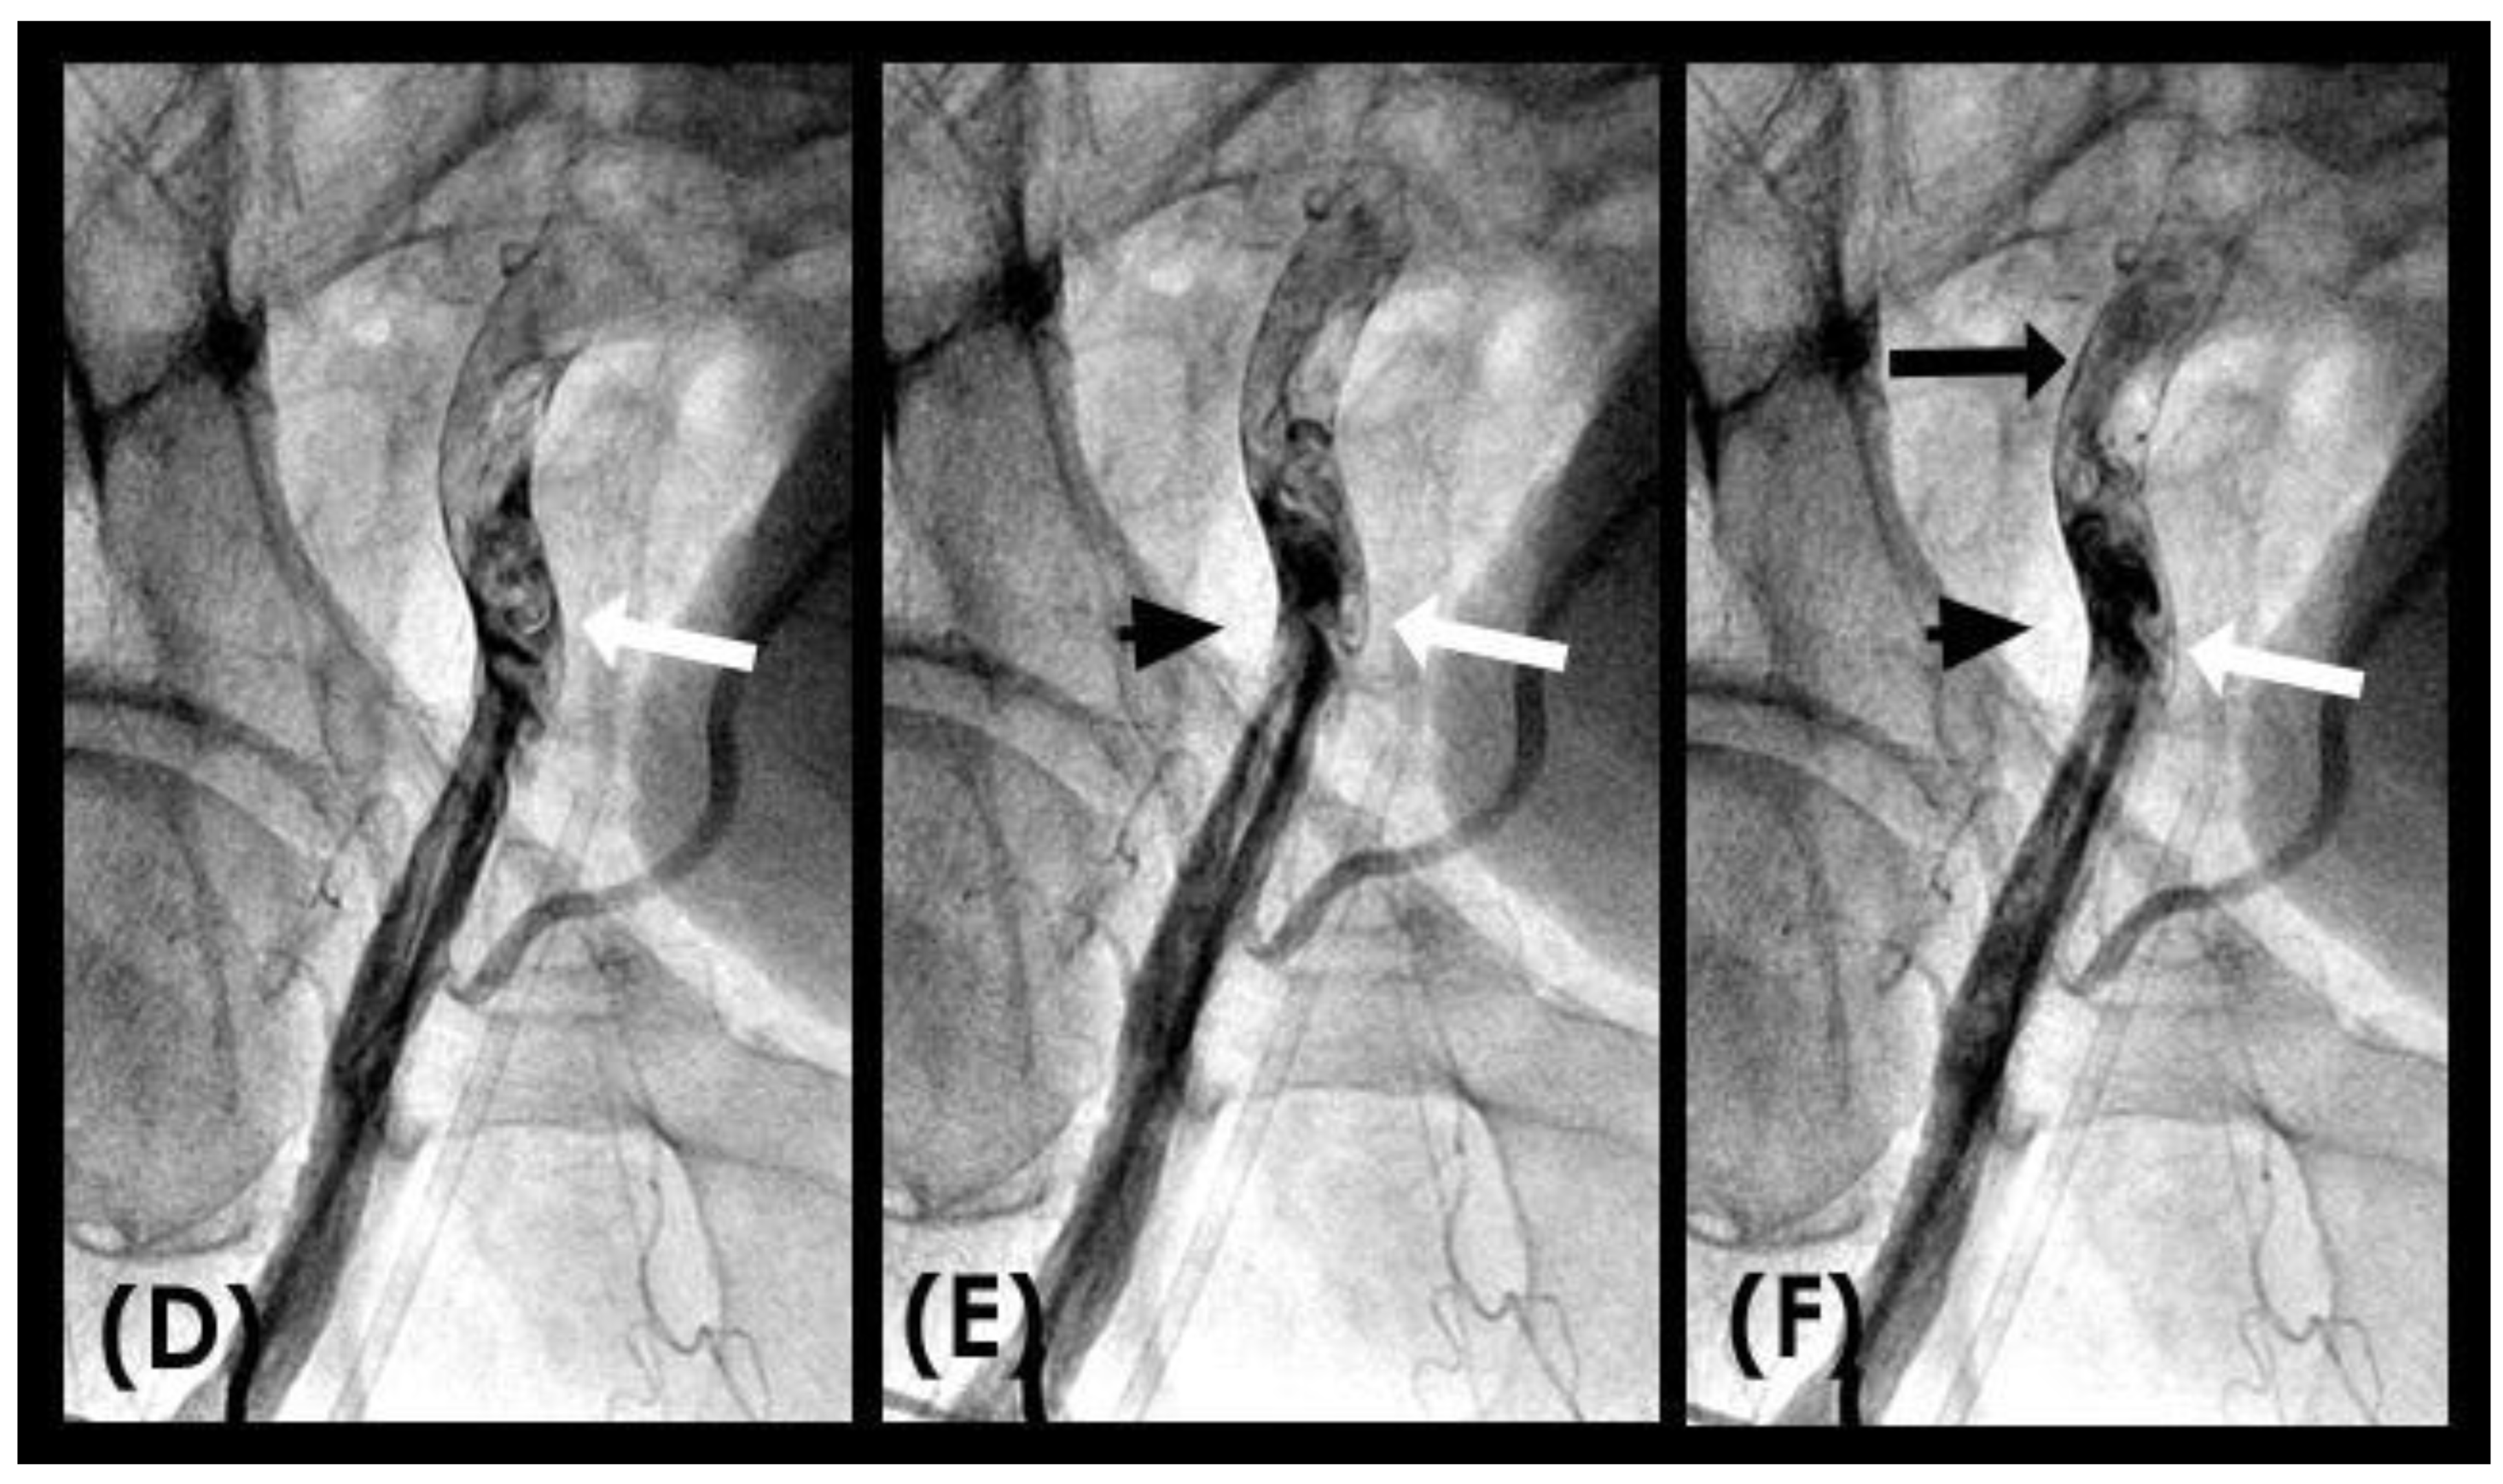

VORTEX formation and degeneration: With the novel angiographic protocol, we observed the following phenomena in the iliac artery during systole: At first, the blood (depicted in white) flowed in an antegrade direction, exhibiting a pointed tip of laminar flow that followed the apical curve of the artery (white arrow) (Figure 10A,B). Subsequently, the pointed tip of the blood flow halted abruptly, with all layers recoiling like a collapsing stack of dominoes (white arrow) (Figure 10C). The tip of the flow then twisted and turned on itself, resembling a vortex (white arrow) (Figure 10D). Sixty-seven milliseconds later, this motion dissipated and was replaced by a mass of black contrast (arrowhead) moving in a retrograde direction along the inner curve (Figure 10E). This black contrast mass gradually expanded, indicating the superior strength of the retrograde flow (Figure 10F). The sharp interface between the blood (white) and the contrast (black) suggested a soft contact between the two liquids (Video S3).

Figure 10.

(A–C) Vortex formation in the iliac artery. This is a sequence of six consecutive angiographic images of the iliac artery. (A) The iliac artery is filled with contrast (in black). (B) Sixty-seven milliseconds later, the blood (homogenously white) is seen moving down with a sharp tip of laminar flow (white arrow). (C) Subsequently, the pointed tip of the blood flow halted abruptly, with all layers recoiling like a collapsing stack of dominoes (white arrow). (D) The tip of the flow then twisted and turned on itself, resembling a vortex. (E,F) This vortical motion dissipated and was replaced by a mass of black contrast (arrowhead) moving in a retrograde direction along the inner curve (black arrow).